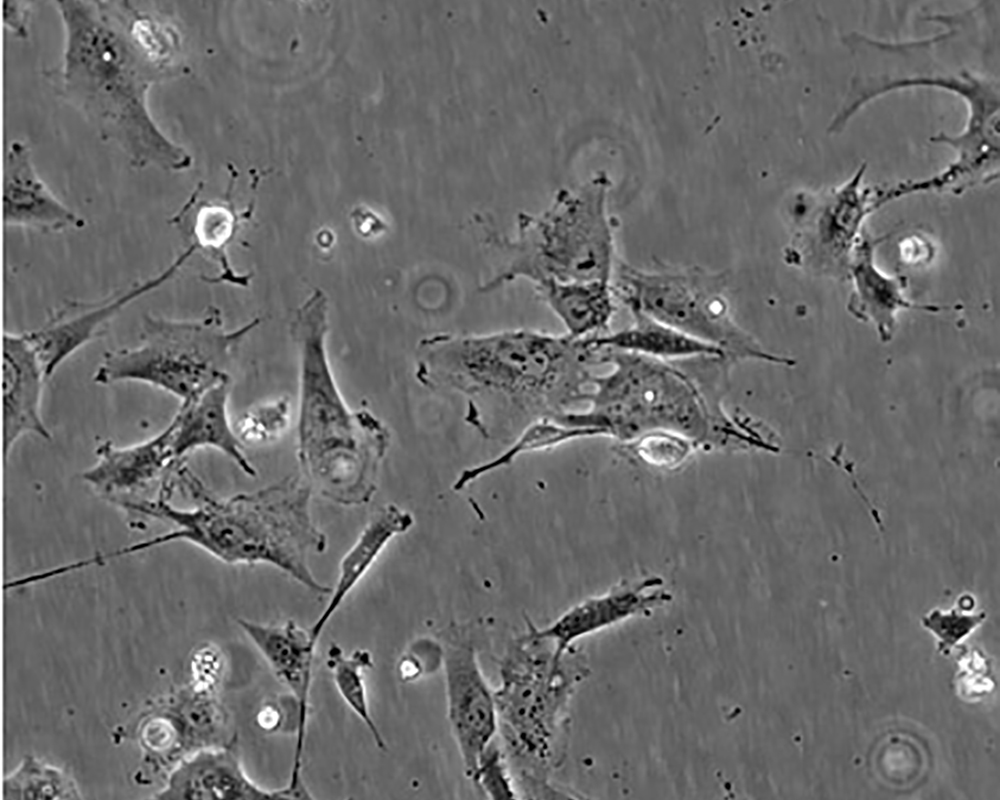

形態(tài)特征 epithelial

細胞描述 The Hs 578T line had a mixed polygonal morphology initially, but a stellate cell type was selected for during passage and by cloning. Aggregates of casein protein granules, desmosomes, tight junctions, lipid droplets and vesicularized smooth endoplasmic reticulum were observed by electron microscopy. As with Hs 578Bst, no estrogen receptors or endogenous viruses were detected.